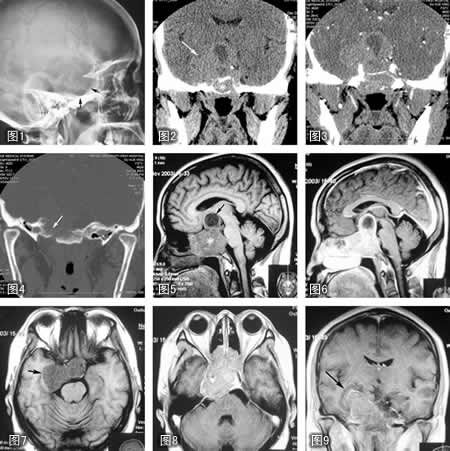

图1 头颅侧位平片,示蝶鞍明显扩大,边界模糊(↑),后床突消失。

图2 冠状位CT平扫,蝶鞍中部水平,可见巨大软组织密度肿块(↑),部分凸入右侧中颅凹,蝶窦内充满肿物。肿瘤上部可见低密度的囊样变。

图3 增强CT,示肿瘤实性部分轻度均匀增强。

图4 CT冠状扫描骨窗,示肿瘤相邻岩骨与枕骨斜坡骨质破坏(↑)。

图5 MRI 正中矢状T1WI像示鞍区巨大软组织肿块()向前下凸入蝶窦、鼻咽上壁,后鼻孔受压。↑示肿瘤上部囊变。

图6 钆增强MRI 正中矢状T1WI,可见肿瘤明显增强。

图7 MRI轴位T1WI。

图8钆增强轴位T1WI。

图9钆增强冠状T1WI,示鞍区肿瘤凸入右侧中颅凹(↑)与后组筛窦。

手术中打开蝶窦即见肿瘤,淡红色,易碎。病理诊断为垂体腺瘤,部分区域生长活跃。, 百拇医药(唐光健)